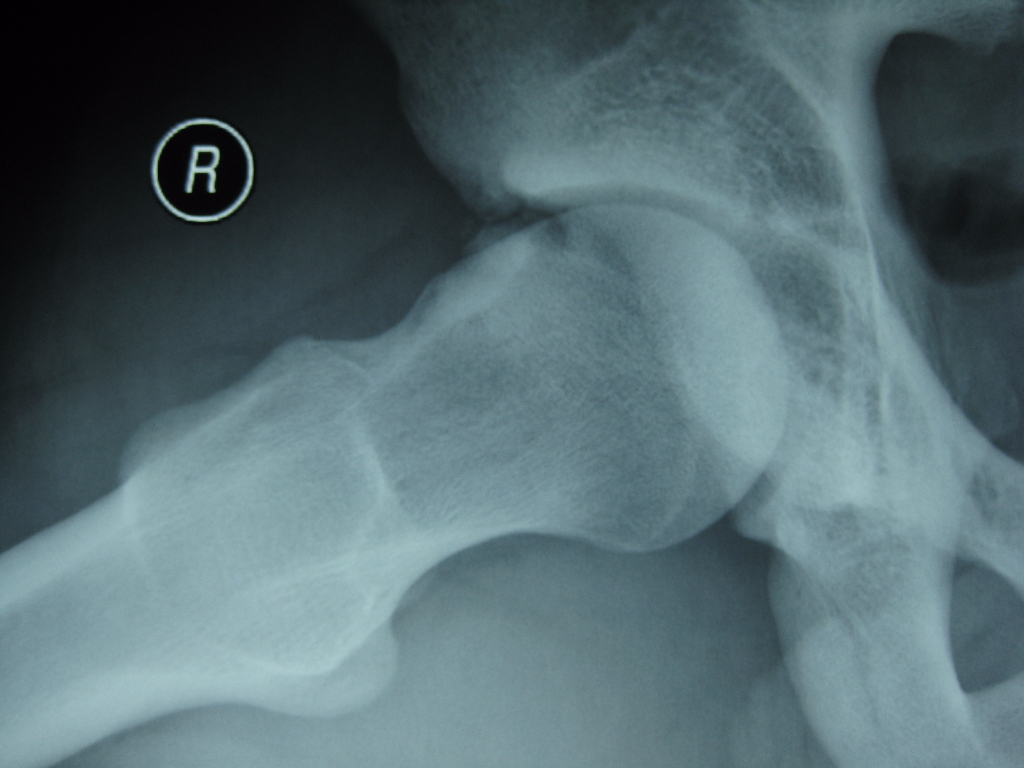

- Imaging Tests: Advanced imaging techniques, such as X-rays and MRI, may be employed to visualise the hip joint’s structure and identify any anatomical abnormalities or signs of cartilage damage.

- Cam Impingement: This occurs when the femoral head is not perfectly round and has an irregular shape, leading to abnormal contact with the acetabulum during hip movements. This deformity often develops during childhood or adolescence.

- Pincer Impingement: This type occurs when the acetabulum (the socket of the hip joint) has excessive coverage of the femoral head, causing the two bones to collide during hip flexion. This can result from structural abnormalities in the pelvis.